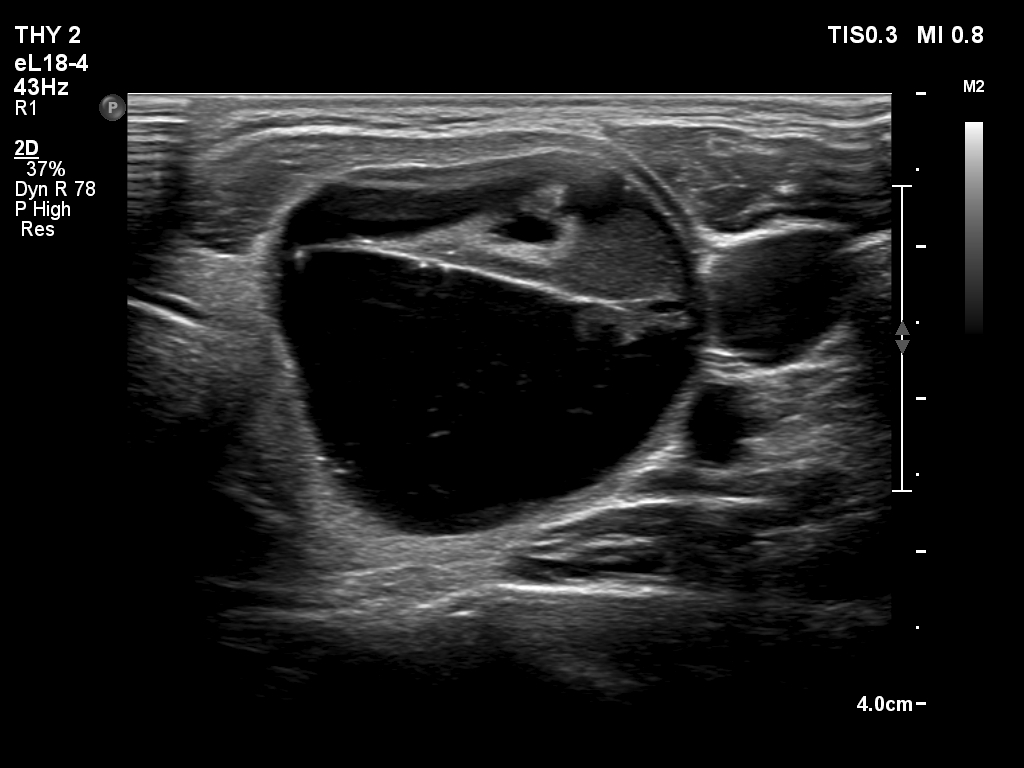

Second session of sclerotherapy (fourth row of images):

Clinical presentation. The patient had no complaints.

Ultrasonography. A minimally hypoechoic-echonormal mass has appeared within the nodule. By compression, we could detect flow of the mass.

This time 2.5 mL fluid was removed and 4.8 mL ethanol was injected. At the end of the session the patient felt a straining pain which lasted for half minute.